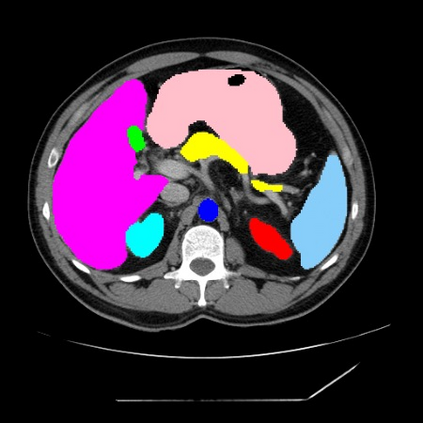

Integrating high-level semantically correlated contents and low-level anatomical features is of central importance in medical image segmentation. Towards this end, recent deep learning-based medical segmentation methods have shown great promise in better modeling such information. However, convolution operators for medical segmentation typically operate on regular grids, which inherently blur the high-frequency regions, i.e., boundary regions. In this work, we propose MORSE, a generic implicit neural rendering framework designed at an anatomical level to assist learning in medical image segmentation. Our method is motivated by the fact that implicit neural representation has been shown to be more effective in fitting complex signals and solving computer graphics problems than discrete grid-based representation. The core of our approach is to formulate medical image segmentation as a rendering problem in an end-to-end manner. Specifically, we continuously align the coarse segmentation prediction with the ambiguous coordinate-based point representations and aggregate these features to adaptively refine the boundary region. To parallelly optimize multi-scale pixel-level features, we leverage the idea from Mixture-of-Expert (MoE) to design and train our MORSE with a stochastic gating mechanism. Our experiments demonstrate that MORSE can work well with different medical segmentation backbones, consistently achieving competitive performance improvements in both 2D and 3D supervised medical segmentation methods. We also theoretically analyze the superiority of MORSE.

翻译:在医学图像分割中,整合高级语义相关的内容和低级解剖特征对于模拟这些信息非常重要。近期基于深度学习的医学分割方法已经显示出很有前景,可以更好地建模这些信息。然而,医学分割的卷积运算符通常在正则化网格上运作,这在本质上模糊了高频区域,即边界区域。我们在这项工作中提出了 MORSE,这是一个设计在解剖学水平上的通用隐式神经渲染框架,用于协助医学图像分割的学习。我们的方法的动机在于隐式神经表示已经被证明比离散化网格表示更有效地拟合复杂信号和解决计算机图形问题。我们方法的核心是将医学图像分割连续地对准粗糙的分割预测和模棱两可的基于坐标的点表示,并聚合这些特征来自适应地精细化边界区域。为了并行地优化多尺度像素级特征,我们借鉴了 Mixture-of-Expert (MoE) 的思想设计和训练我们的MORSE,使用随机门控机制。我们的实验表明MORSE可以很好地与不同的医学分割后骨干结合在一起,始终在2D和3D监督医学分割方法中实现了有竞争力的性能改进。我们还从理论上分析了MORSE的优越性。